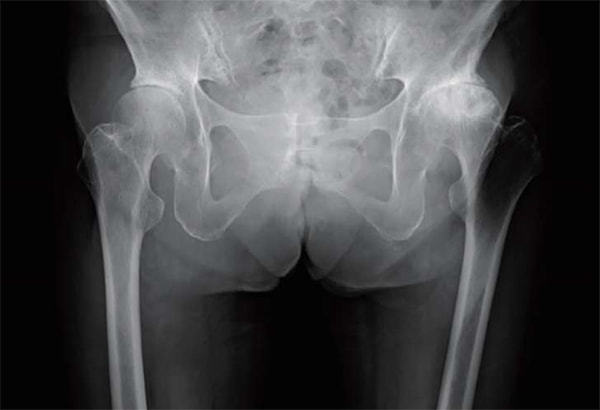

仰臥位股関節Xp

立位股関節Xp

立位で骨盤後傾を伴う

術後 立位股関節Xp

人工股関節置換術において従来の後側方アプローチ(Posteo Lateral Approach)に加えて、2015年より前方アプローチ(Direct Anterior Approach)を積極的に取り入れて参りました。

これは脱臼率の低下に加えて、筋間アプローチによる低侵襲手術を提供するという目的によるものです。これにより在院日数は低下し、術後の姿位制限を撤廃したことで、前述のスポーツ復帰率の向上を図ることができるようになりました。また、高齢化に伴い生じる脊椎変形、脊椎固定術後の矢状断アライメントの変化に対応できるよう、CUPは透視を用いて動的に評価しながら至適位置に設置することで良好なstabilityが得られています。